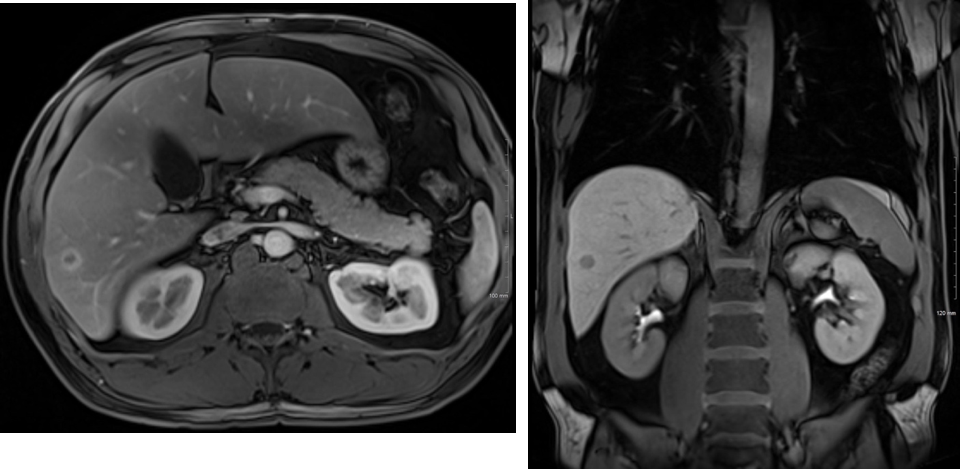

Case Presentation: A 52-year-old male presented for an evaluation of hematuria. The complete blood count, basic metabolic panel and liver function tests were within normal limits. A CT abdomen and pelvis showed an incidental, 1.5 cm lesion in the right hepatic lobe. Following fine needle aspiration biopsy of the lesion, the tissue demonstrated a slightly irregular hepatic duct proliferation, for which a differential diagnosis of bile duct adenoma (BDA) and well-differentiated cholangiocarcinoma was considered. The serum levels of tumor markers including alpha-fetoprotein, carbohydrate antigen 19-9, and carcinoembryonic antigen were normal and hepatitis serologies were negative. An MRI was obtained to better ascertain the lesion, which demonstrated a 1.1 x 1.1cm lesion within the right hepatic lobe, segment 6 (Figure 1). The case was discussed on tumor board and the decision was made to pursue a hepatic resection of segment 6-7. On gross examination, the specimen was serially sectioned, revealing an ovoid, well-circumscribed, white-tan, firm lesion measuring 1.4cm in greatest dimension, and located 0.5cm from the hepatic capsule. Microscopically, there was a well-circumscribed lesion composed of small biliary-type glands in tubular and branching trabecular patterns (Figure 2). There were a mild nuclear enlargement and inconspicuous mitotic activity. The lesion was well-delineated and the interphase with hepatocytes was regular without infiltrative growth. Immunohistochemically, CD56 was focally positive in the tumor. Because of the size of the tumor as well as subtle nuclear atypia, the most appropriate diagnosis was atypical bile duct adenoma.